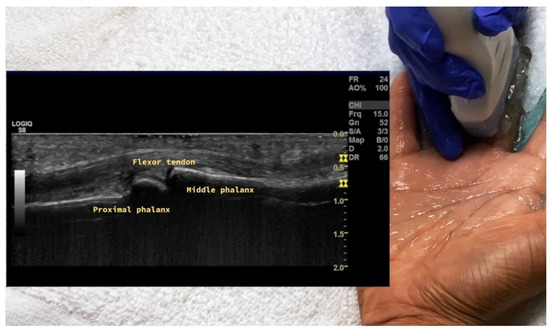

4.1. Evaluation of the Fingers

4.1.2. Volar Aspect